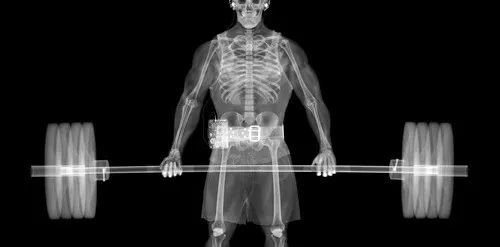

文章插图

同为72岁、BMI(身高-体重指数)= 25女性大腿肌肉的横断扫描 , 左图为正常 , 右图是肌少症患者 。